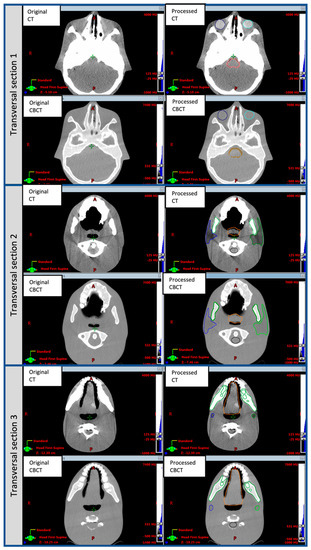

The original and post-processed CT and CBCT phantom images in three different transverse sections are shown in Figure 2. Table 1 reports the HU values of OARs in the original and processed CT and CBCT phantom images. Both post-processed phantom image sets have been made publicly available as additional downloadable material for this paper, as Supplementary Material.

Figure 2.

Original and post-processed CT and CBCT transverse sections of the CIRS ATOM Max Dental and Diagnostic Head Phantom Model-711 used in the method presented for DIR accuracy evaluation. Sections were chosen to visualize organs of interest. The HU values of parotid glands, larynx, oral cavity, brainstem and eyes were digitally modified using MATLAB and CERR tools, as described in Section 2.1.

Table 1.

Original and post-processed CT and CBCT transverse sections of the CIRS ATOM Max Dental and Diagnostic Head Phantom Model-711 used in the method presented for QA of DIR. The HU values of parotid glands, larynx, oral cavity, brainstem and eyes were digitally modified using MATLAB and CERR tools, as described in Section 2.1. HU values for original and post-processed CT and CBCT phantom images reported in the table referred to a ROI of 20 × 20 pixels.